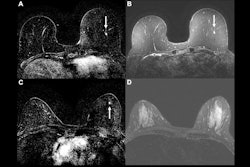

Abbreviated axial MRI images show a 7-mm irregular mass with irregular margin (arrows) in the right upper inner quadrant with early rapid enhancement (BIRADS 4). The participant was recalled and underwent an MRI-guided vacuum-assisted biopsy that showed sclerosing adenosis with microcalcifications and usual ductal hyperplasia and focal apocrine metaplasia. On the full-protocol images (not shown), the lesion was T2-weighted hypointense and showed diffusion restriction and washout kinetics in the delayed phase, characteristics that would not have reversed the decision to recall the participant.RSNA